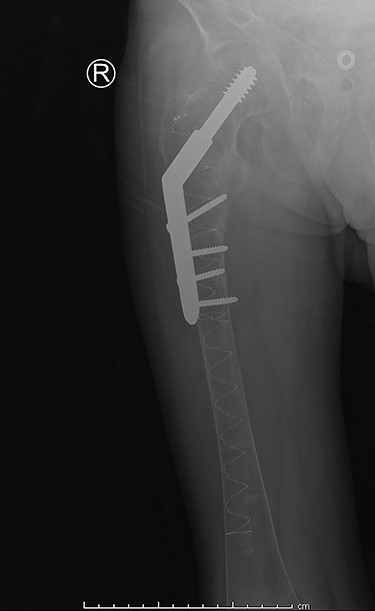

Postoperative

Our patient was discharged from the hospital 14 days after the surgery. The long hospital stay was mostly due to the management of the renal Fanconi syndrome. He was able to mobilize with crutches at time of discharge. The in-hospital stay was without complications. Eight weeks postoperatively our patient returned to our outpatient clinic. Full mobilization was possible and there was a full range of motion. Conventional imaging showed an adequate position of our hybrid osteosynthesis (Fig. 3) and an almost completely healed fracture site.

Post-operative anterior–posterior view: DHS osteosynthesis with intramedullary bone enhancement.

In this case, we decided against a cephalomedullary device, due to the poor bone quality of the femur and the concomitant high risk of iatrogenic fracturing. Therefore, we reinforced the femoral shaft using Illuminoss before fixation with a DHS. This fixation is comparable to traditional intramedullary fixation [4]. Placement of the omega 3 implant was possible, due to the immediate stability that the polymer provides. This combination of reinforcing with Illuminoss and fixation with the omega 3 implant provides the same biomechanical benefits as a traditional cephalomedullary device.